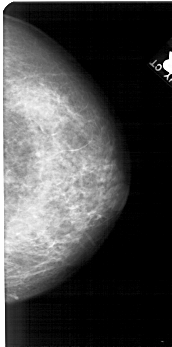

A_1555_1.RIGHT_CC

RIGHT_MLO LINES 5491 PIXELS_PER_LINE 2866 BITS_PER_PIXEL 12 RESOLUTION 43.5 NON_OVERLAY